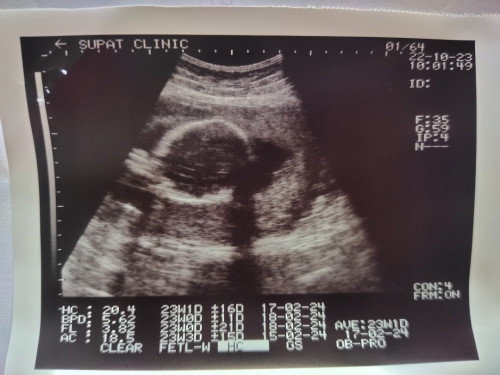

15กุมภา ลูกชายค่าา💖

ลูกชายจ้า กุมภา67🩷